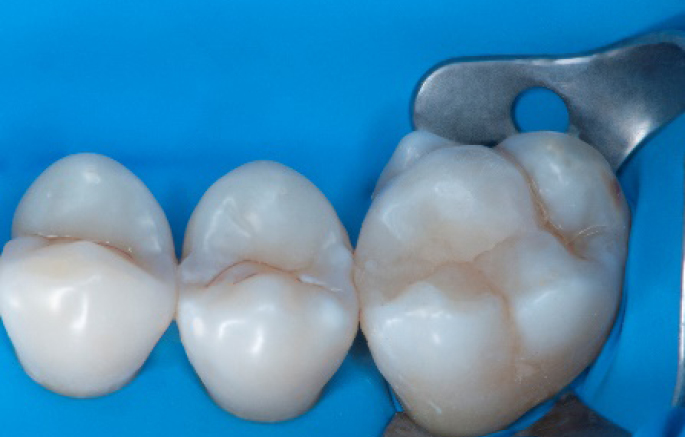

Step 11:

Occlusal surface restored using Spectra ST4 composite in shade A2.

Step 12:

The situation after rubber dam removal.